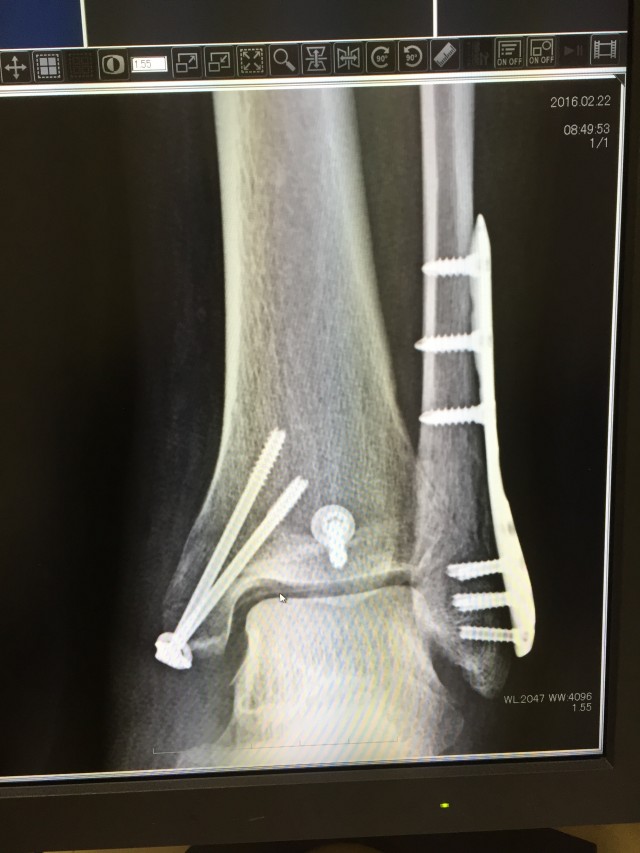

レントゲンの写真は記念に撮らせてもらったので最後に載せますね←

こんなサイボーグになりましたとさw